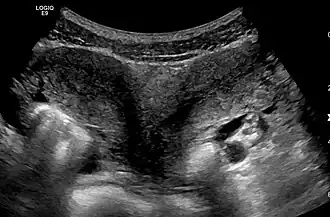

Uterus didelphys[1], uterus didelphus[2] of uterus didelphis is een aandoening waarbij de baarmoeder dubbel aangelegd is, zoals bij de nieren. Beide baarmoeders hebben allebei een eigen baarmoedermond en soms heeft de vrouw ook twee vagina's. Elke baarmoeder heeft zijn eigen eileider en een eigen eierstok.